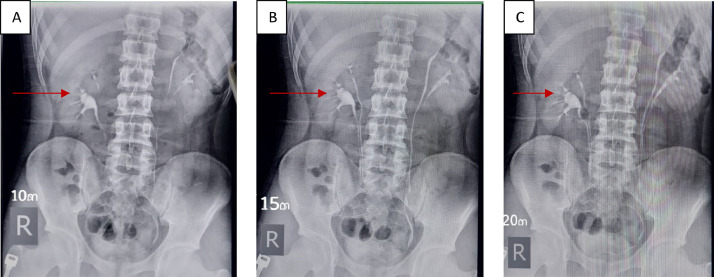

Fig. 1.

The figures showed bilateral complete ureteral duplication; (A) 10-minute postinjection, (B) 15-minute postinjection, (C) 20-minute postinjection, the red arrows demonstrated hydronephrosis in the lower pole of the right kidney, while the upper pole appeared normal.